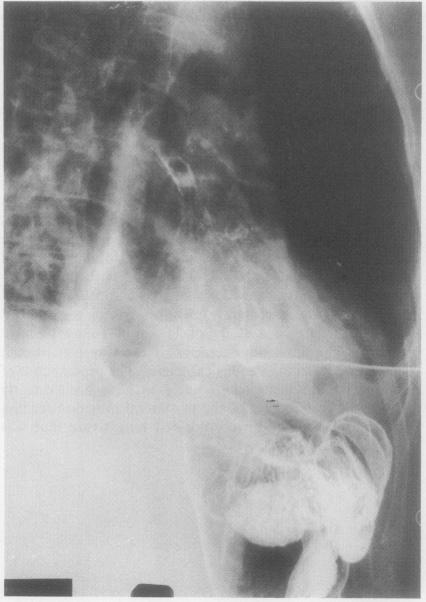

Colobronchial fistula: a late complication of appendicitis.

Thorax. 1988 May;43(5):420-1. doi: 10.1136/thx.43.5.420.

DOI:10.1136/thx.43.5.420

PMID:3194871

Colobronchial fistula: a late complication of appendicitis.结肠支气管瘘:阑尾炎的一种晚期并发症。